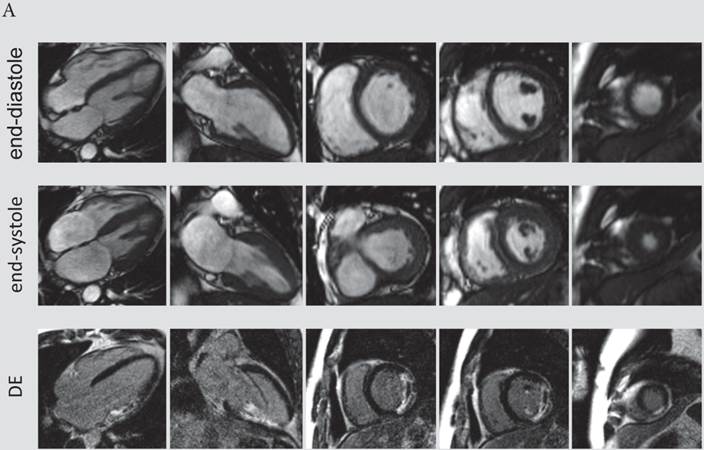

The presence and extent of microvascular obstruction on DE-CMR was significantly correlated to QTd-Rrel (r=-0.725, p<0.001 and r=-0.719, p<0.001), respectively. Patients in the 1st tertile of QTd-Rrel had the highest prevalence (69%) and extent of microvascular obstruction (4.1% of LV mass), and patients in the third tertile of QTd-Rrel showed the lowest (0%). A typical CMR scan of patients with low and high QTd-Rrel post revascularization is shown in figure 3a and 3b.

Figure 3

A) CMR scan of an 63-year-old male exhibiting only a minor reduction of QTd-Rrel post revascularization (QTd-Rrel 1st tertile). This patient had extensive, predominantly transmural myocardial infarction (average infarct transmurality: 95%, QTd-Rrel :0%) with presence of microvascular obstruction. B) A typical CMR scan of a patient with high reduction QTd-Rrel . This 60-year-old male was categorized to the 3rd tertile of QTd-Rrel . CMR images showed limited, non-transmural infarction (average infarct transmurality: 22%, QTd-Rrel: 80%).